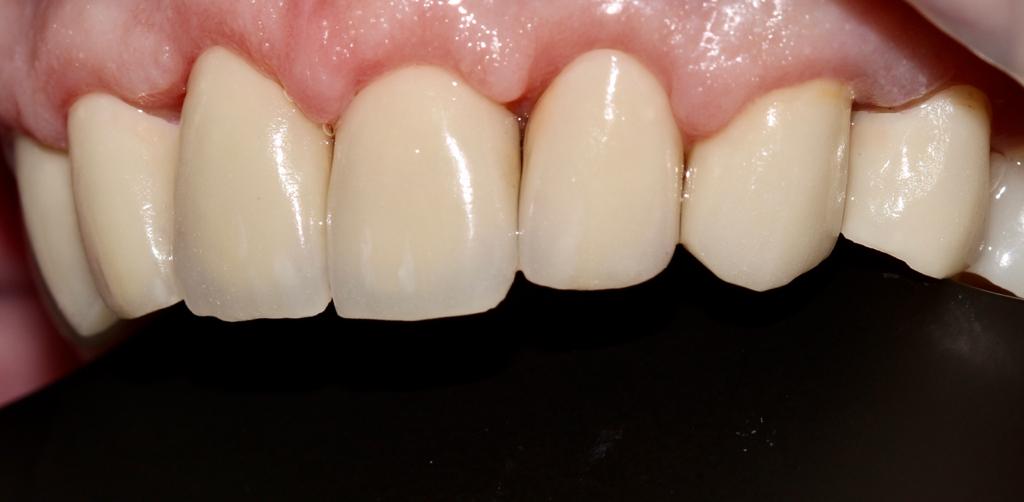

Белые виниры BLEACH

Все чаще стали поступать заказы на виниры цвета BLEACH. Очень красивый результат. Улыбка становится очень красивой.

Это виниры на рефракторе . 12 зуб коронка на оксиде циркония.